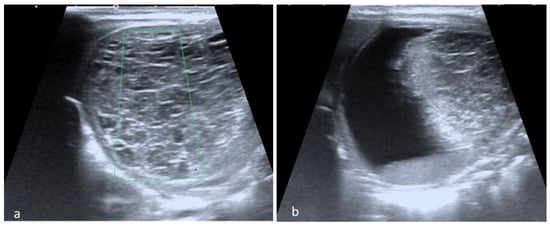

All patients were examined at the hospital admission by experienced physicians certified in Maternal and Fetal Medicine, using high-resolution ultrasound devices equipment Voluson E10 or Voluson 730 Expert (GE Healthcare Austria GmbH & Co OG.) available during that period, following a standardized protocol The Nussbaum criteria [13] were used to define the cysts type. Therefore, a fetal ovarian cyst is defined as simple if it is completely anechoic and has a thin wall (Figure 1a). By contrast the cyst is defined as complex if it is multilocular or unilocular with echogenic content, clot retraction clot, fluid-debris level (Figure 1b).

Figure 1. Cyst’s classification according to Nussbaum criteria: (a) Simple cyst with thin wall and anechoic aspect, (b) complex cyst with intracystic septation.